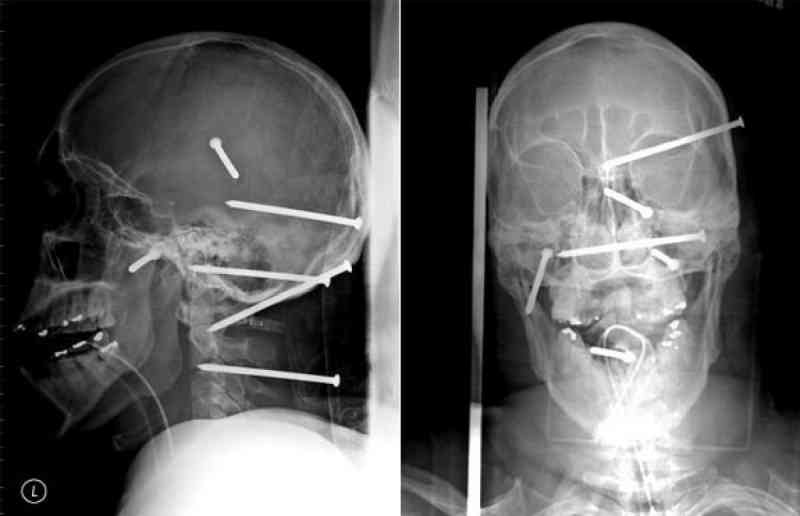

2. While working as a constructor, Isidro Mejia fell off the roof and accidentally shot 6 nails in his head with a nail gun as he landed. Miraculously, he was okay.